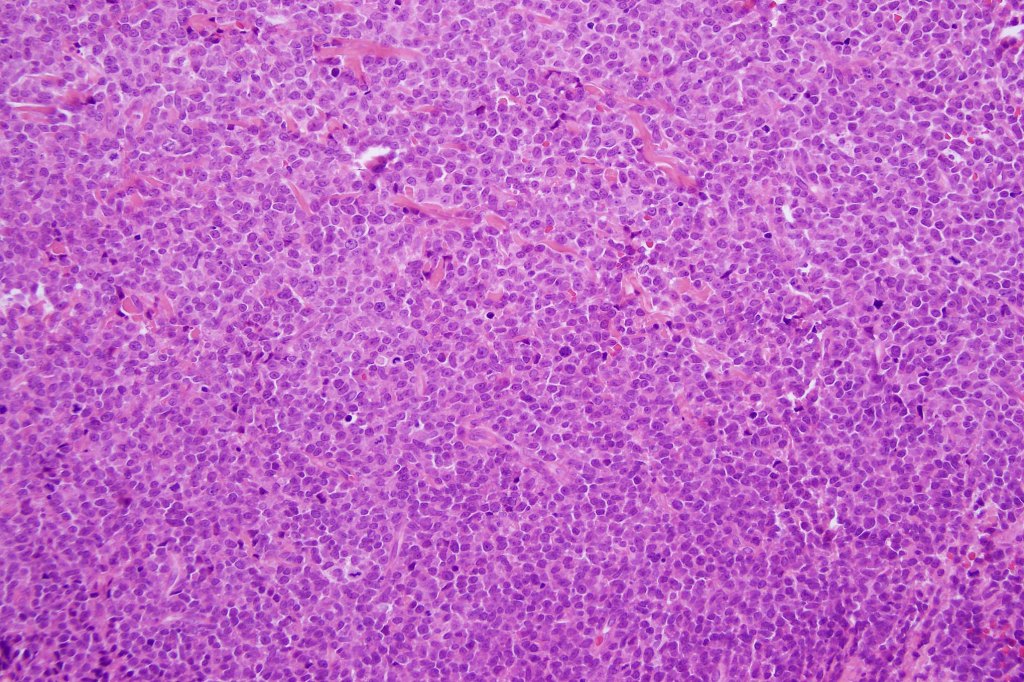

Histological features

. Monotonous blast cells with gray-blue cytoplasm & irrregular vesicular nuclei with prominent nucleoli

. Marked ki67 expression